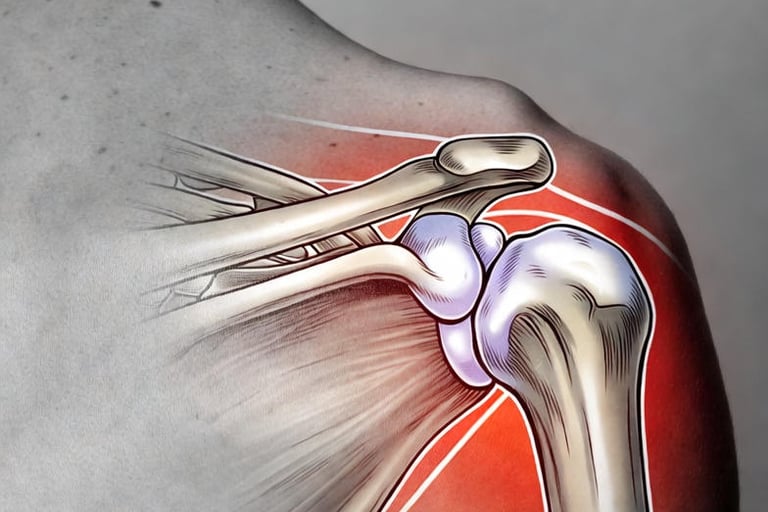

La capsulite rétractile est une inflammation de la capsule articulaire de l’épaule, cette enveloppe fibreuse qui entoure l’articulation. Elle provoque une rigidité progressive, comme si votre épaule « gelait » littéralement. Contrairement à une simple tendinite, cette pathologie évolue en phases distinctes :

L’embolisation de la capsulite rétractile est une innovation récente qui cible la cause profonde de l’inflammation : l’hypervascularisation. Dans une épaule gelée, de petites artères anormales se développent autour de la capsule, alimentant le processus inflammatoire et la douleur.